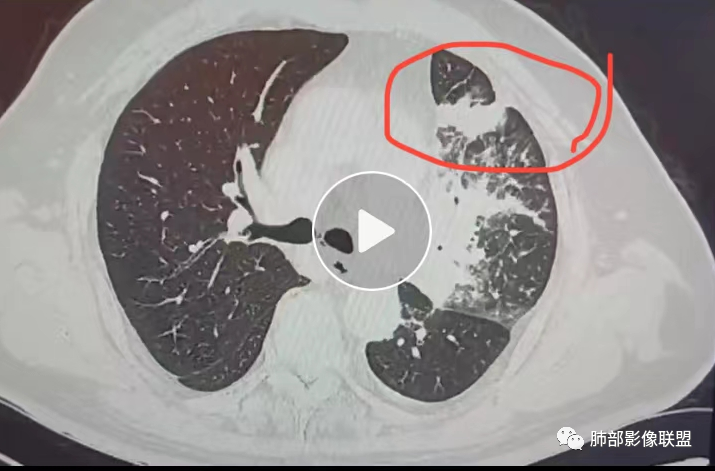

秦化君:左肺上叶不均匀实变影,边缘部分清晰,近端支气管通畅,纵隔及左肺门淋巴结肿大,左上肺局部淋巴管炎。左侧胸腔积液,心包积液。考虑恶性病变,淋巴瘤?腺癌?

飞鹰行动:老年男性,左肺病灶,边缘模糊,右肺下叶可见小片状阴影,纵膈淋巴结稍增大,心包少量积液,考虑感染性病变,结核?肺克?

宇宙:老年男性,糖尿病史,左肺上叶及舌叶实变伴局部小叶间隔增厚,沿支气管血管束分布,密度不均,肺门浓密,支气管未见明显阻塞,考虑腺癌,鉴别结核。

我只是邓较瘦:考虑多原发腺癌伴癌淋,鉴别淋巴瘤。

良孑:左上叶不张,左上叶支气管渐进行狭窄,不张内支气管走行僵直呈串珠状,纵隔内淋巴结肿大,左侧斜裂胸膜上多发结节,纵隔旁小叶间隔增厚,高龄,炎性标志物正常,首先考虑恶性占位腺癌,其次鉴别一下支气管TB。

放射线:左肺上叶实变,沿着支气管走行分布,支气管部分阻塞部分扩张,周围小叶间隔及中轴间质结节状增厚,纵隔淋巴结肿大,心包积液,考虑腺癌伴癌淋,心包转移,右肺磨玻璃结节并胸膜牵拉凹陷,考虑IAC。

谢加平:左肺门旁团块影,上叶支气管开口严重狭窄,中轴及小叶间隔增厚(示淋巴回流受阻),左肺叶阻塞性肺炎,纵隔淋巴结肿大,支持恶性,肺腺Ca,另见右肺上叶后段胸膜下亚实性结节,叶间胸膜牵拉明显,考虑lAC。甲状腺右叶结节性甲状腺肿?支气管镜检查!

衡妈:左肺门见大片状不规则软组织密度,左肺上叶近端支气管管壁僵直,分支堵塞,病灶周围结构紊乱,小叶间隔增厚且伴结节感,考虑淋巴管炎;纵隔淋巴结肿大。炎性指标正常,考虑肿瘤性病变,腺癌伴周围癌性淋巴管炎可能,鉴别结核。

流心明智:男,69,咳嗽、咳痰1月。胸部CT:甲状腺右叶结节;左上肺大片状不规则软组织密度影,病灶周围结构紊乱,中轴间质不均匀增厚,小叶间隔结节样增厚,支气管充气征,枯枝?;右上叶后段胸膜下mGGN,周围磨玻璃界清,叶裂牵拉凹陷;纵隔多发淋巴结肿大。考虑肿瘤,腺癌伴癌淋?转移瘤?鉴别结核。

离殇:老年男性,双肺多发病变,以左肺较著,右肺上叶后端可见混合磨玻璃病变,边缘清晰,病灶内支气管扩张,考虑腺癌?慢性炎症?左肺片状/斑片状密度增高影,左肺多发小叶间隔增厚,未见明显结节影,支气管未见明显截断征象,肺门/纵隔淋巴结增大,心包及左侧胸腔少量积液,考虑恶性,腺癌?结核?;甲状腺右侧叶类圆形密度减低影,边缘尚清,考虑结节性甲状腺中,左侧肩胛骨下部肌肉内脂肪密度影,考虑脂肪瘤。

AAA张春雨:肺部联盟病例:纵隔向左移位,提示慢性疾病,心包积液,左肺上叶内侧段不张,纵隔淋巴结肿大但不是肿瘤转移的填塞式的大淋巴结,考虑支气管内膜结核,结核性心包炎。

南边:问个问题:病灶累及整个上叶,如果考虑肺癌:中央型?周围型?中央型:支气管堵塞:远端不张,符合吗,不符合,周围型:外周朝内带推移:符合吗?如果恶性:那就是考虑转移?

三、影像表现:左肺上叶多发片状高密度影,散在,边缘模糊,支气管壁稍增厚,中轴间质、小叶间隔增厚、有结节感,左肺上叶前段病灶可见胸膜增厚,部分小支气管不能分辨;右肺上叶后段混合磨玻璃结节,边界清,邻近胸膜凹陷;纵膈淋巴结肿大;心包增厚;左侧少量胸水。此外,扫及右侧胸腔内甲状腺肿;左侧肩胛骨旁肌群内脂肪瘤。